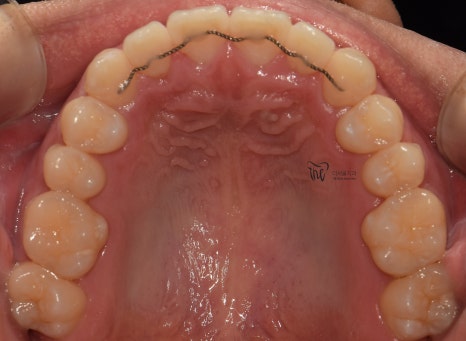

『11개월 소요, 치료 결과 안내』

따라서, 11개월 이라는 기간이 소요되어서

치료 종료가 되었습니다.

치열이 많이 가지런하게 펴진 것을 볼 수 있고,

그간 치과에 자주 오셨기 때문에 교정유지기 를

붙여드리면서 f.u 을 자주 받으러 오셔라..

라는 안내를 드렸었습니다.